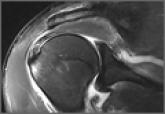

Successful Nonoperative Management of HAGL (Humeral Avulsion of Glenohumeral Ligament) Lesion With Concurrent Axillary Nerve Injury in an Active-Duty US Navy SEAL

Humeral avulsion of the glenohumeral ligament (HAGL) is a lesion that has been recognized as a cause of recurrent shoulder instability.